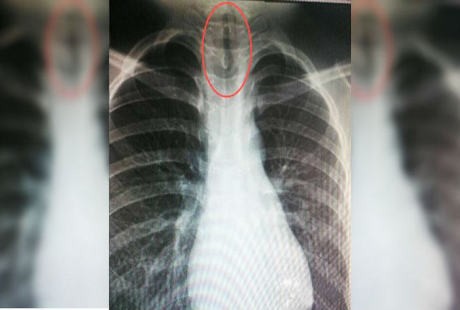

Lintah ini diperkirakan tumbuh di dalam saluran pernapasan bocah berusia 11 tahun itu selama beberapa minggu. Selain itu karena lintah ini tumbuh di dalam saluran pernapasan Chien, maka tiap kali lintahnya bergerak, ia akan menutup saluran tersebut dan menyebabkan Chien mudah pingsan.